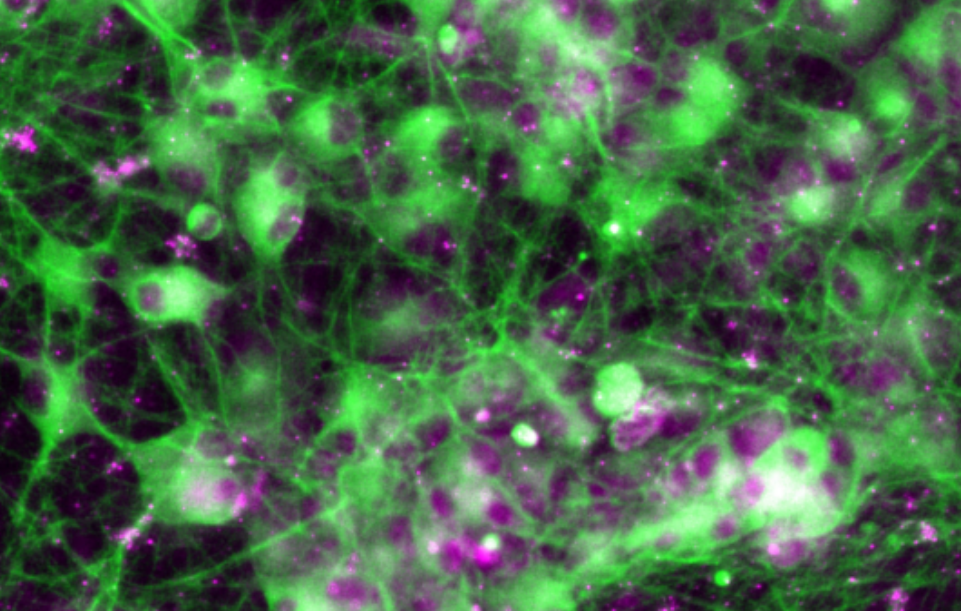

iPS 细胞衍生神经元